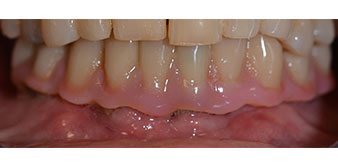

La paziente, 64 anni, presenta una dentatura residua di denti 38, 33 e 43 e una protesi combinata innestata nella mandibola (Fig. 1 e 2).

dentatura residua

Fig. 1